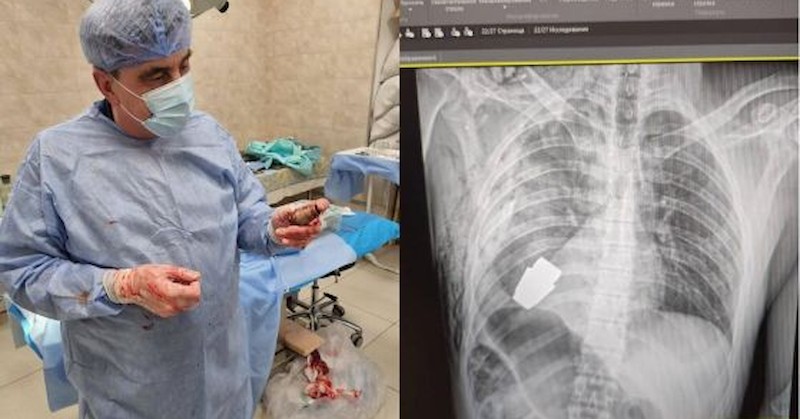

Военни лекари в Украйна са извадили граната ВОГ от гърдите на боец, която не е експлодирала. В операционната, дружно с украинските лекари, е имало и двама сапьори, оповестява немското издание „ Шпигел “, съобщи.

Украинският боец е потърпевш по време на обстрел. Тогава в гръдния му панер се забива гранатата.

Според изнесената информация е съществувала възможност тя да избухне всеки миг и по тази причина е осъществена незабавна интервенция, ръководена от най-опитния хирург в украинските въоръжени сили.

Хирурзите не са употребявали електрокоагулация – способ за прекъсване на кървенето или рязане на тъкани посредством потреблението на ток.

„ Мисля, че този случай ще остане в медицинските учебници “, споделя представителят на военномедицинските сили Евгения Сливко, представена от немското издание. По думите ѝ интервенцията е била сполучлива и боецът се възвръща.

Хана Маляр е разгласила във Facebook фотография с основния хирург, който държи изваденото устройство. На нея ясно проличава " запалката ", в чийто край има скоба за задействане.

„ Мъжът е изпратен за рехабилитация, положението му е устойчиво “, оповестява и Антон Геращенко, консултант към вътрешното министерство на Украйна. Говорителят на военномедицинските сили в страната прецизира, че боецът е на 28 години.